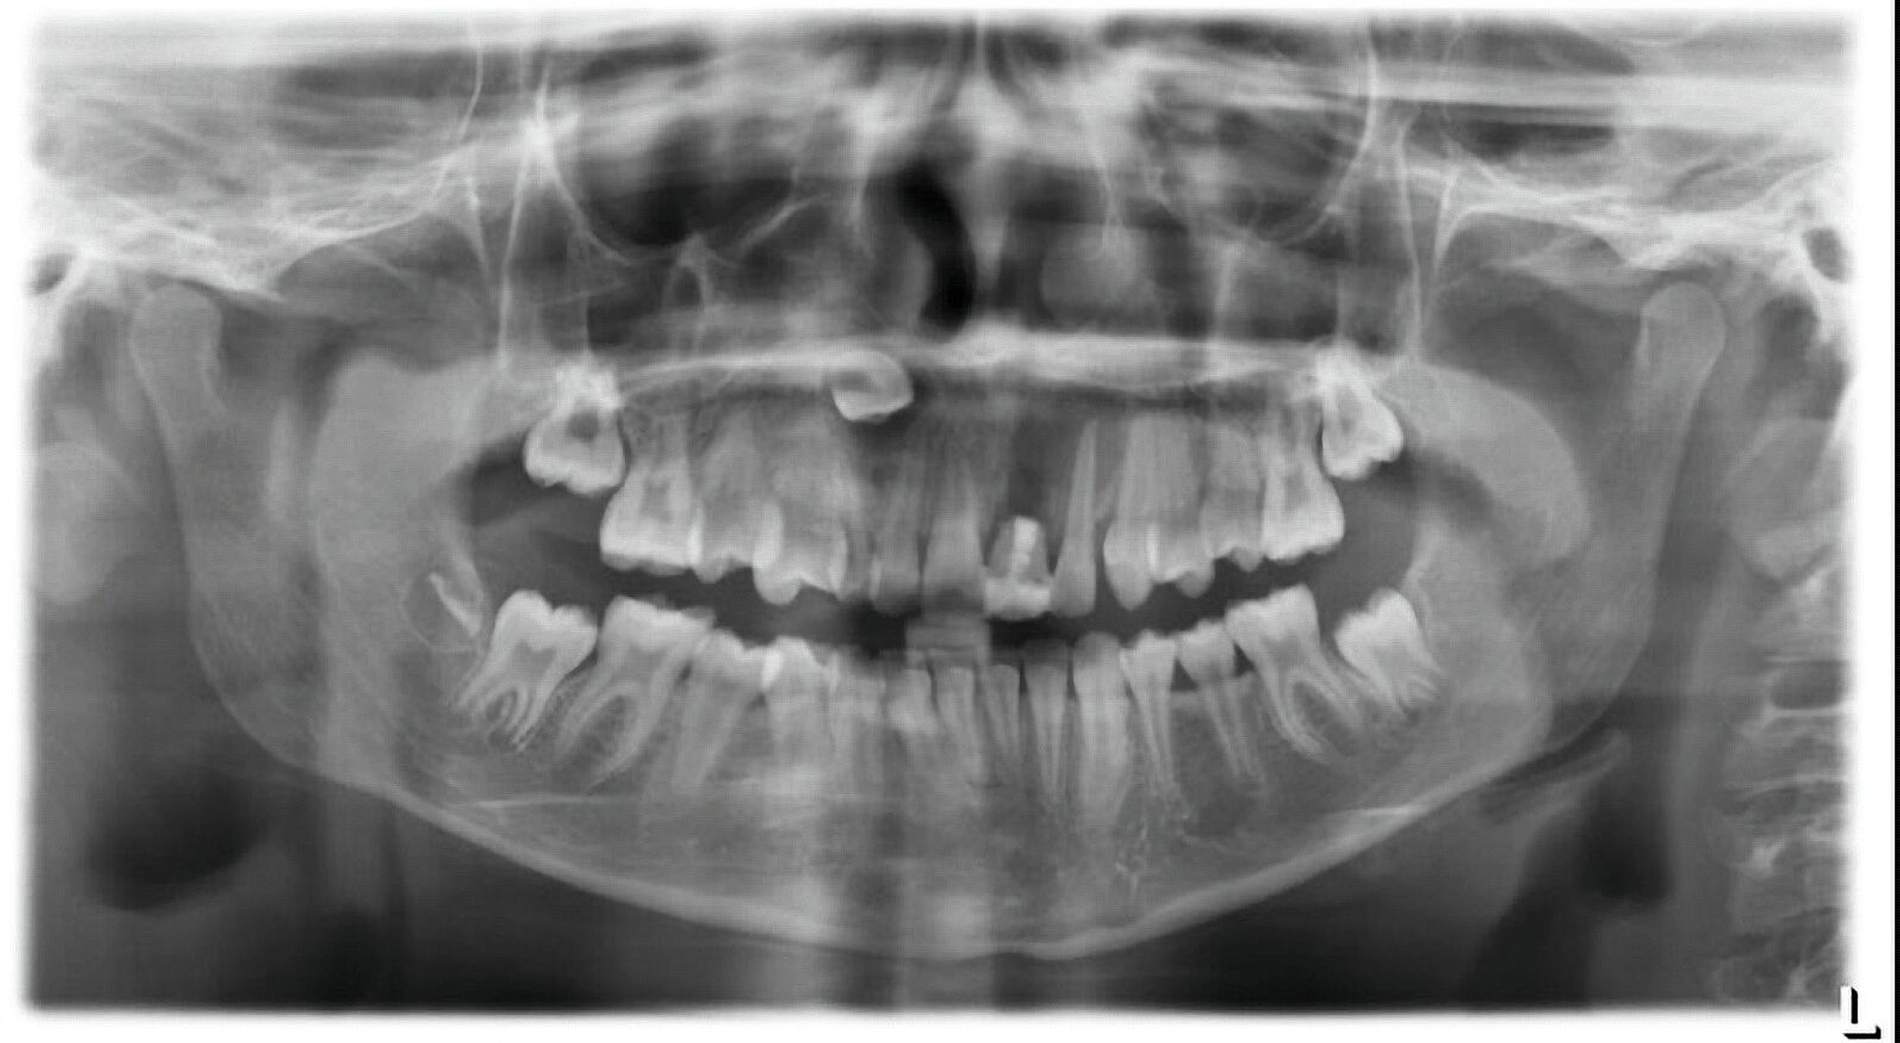

Zwei Jahre nach einem komplexen Zahntrauma mit komplizierter Kronenfraktur 21 und endodontischer Versorgung stellte sich eine elfjährige Patientin mit nun ausgedehnter apikaler Beherdung am Zahn 21 bei uns vor (Abbildung 1). In ihrer Krankengeschichte hatte die Patientin im Alter von vier Jahren eine Leukämie überwunden. Es wurden keine weiteren gesundheitlichen Probleme angegeben. Im OPG zeigt der Zahn 21 eine periapikale Aufhellung im Sinne einer Parodontitis apicalis chronica mit nun akuten klinischen Schmerzen (Abbildung 1).

Zur weiteren Abklärung wurde eine dreidimensionale Aufnahme durchgeführt (DVT). Dabei bestätigte sich die erhebliche Osteolysezone im apikalen Bereich des vormals traumatisierten Zahnes 21. Der Zahn 13 stellt sich hoch verlagert am Nasenboden dar, während es bei dem persistierenden Milchzahn 53 zu einem natürlichen Lückenschluss in regio 13 gekommen ist (Abbildung 2).